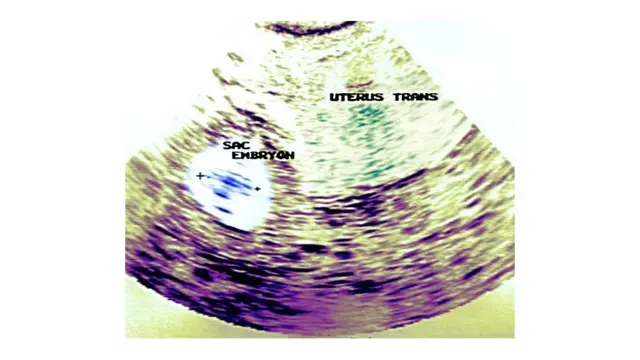

मी पडद्यावरच्या स्कॅनकडे पाहिलं.

तिच्या गर्भाशयाला लागूनच रिंगसारखं काहीतरी दिसत होतं.

मी स्क्रीनच्या जवळ जात नीट निरखून पाहिलं... Ectopic Pregnancy…गर्भाशयाबाहेर झालेली गर्भधारणा.

कधीकधी गर्भधारणा ही गर्भाशयाच्या आत न होता, त्याच्या बाजूच्याच नलिकेत ( Fallopian Tube) होते. नलिकेचा आकार कमी असल्याने गर्भाची वाढ दोन महिन्यांपेक्षा अधिक होऊ शकत नाही. वर्षिता गर्भाचा आकार तपासत होती, "मॅडम 4.2 सेंटीमीटर्स," तिने सांगितलं. म्हणजे हृदयाचे मंद ठोके असणारा अतिशय लहान गर्भ.